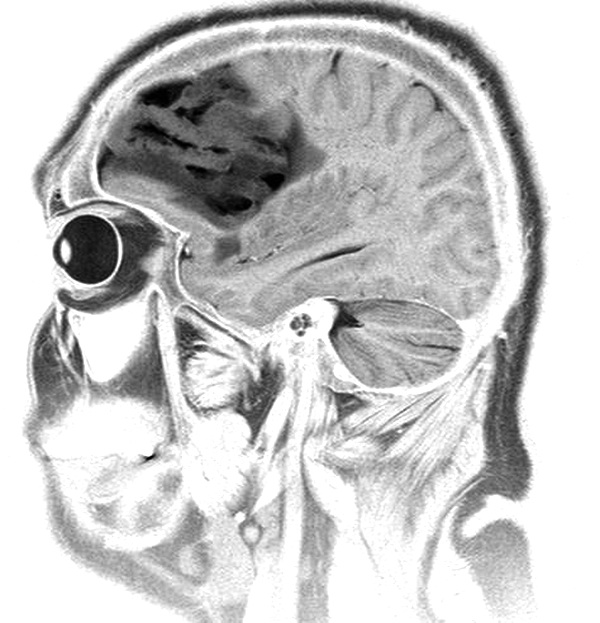

Рис.1. Положение больного с хронической сердечной недостаточностью.